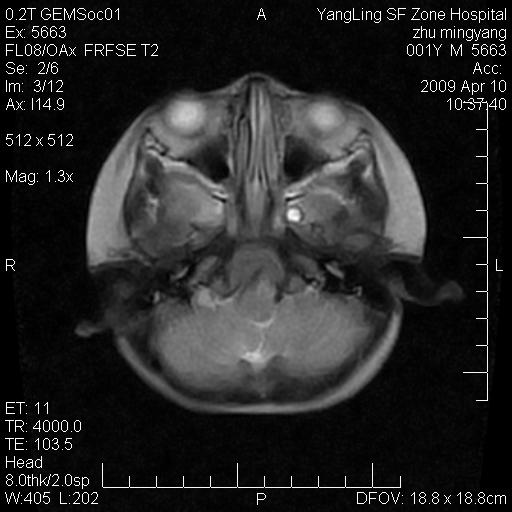

患者:1岁半,两天前外伤收住我院,ct检查小脑占位

考虑星形细胞瘤,建议增强

髓母细胞瘤或血管母细胞瘤,增强后可以鉴别;影像资料见 <。鱼博浪老师的《中枢神经系统ct与mr鉴别诊断》 小脑部肿瘤章节。

髓母细胞瘤或血管母细胞瘤!支持!

支持考虑髓母细胞瘤

考虑----髓母细胞瘤可能性大

考虑髓母细胞瘤或室管膜瘤。

支持髓母细胞瘤。

考虑髓母细胞瘤。

考虑髓母细胞瘤或星形细胞瘤

考虑髓母细胞瘤.

考虑髓母细胞瘤可能性大。

小脑肿瘤.考虑髓母细胞瘤可能.

就病灶部位及临床资料首先考虑髓母.